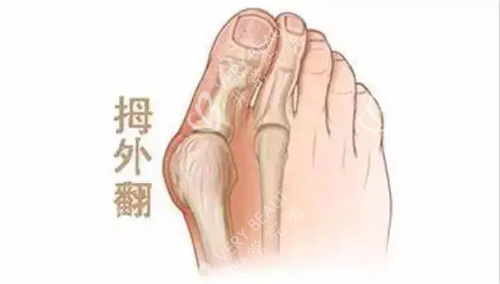

在追求美丽与健康的道路上,大脚骨问题成为了许多人的困扰。它不仅影响足部美观,还可能引发疼痛与功能障碍。北京广济医院凭借其在大脚骨治疗领域的卓然表现,成为了众多患者的信赖之选。下面,让我们深入了解一下这家医院。

北京广济医院是一家集医疗、教学、科研于一体的现代化综合性医院,位于北京市丰台区。它是经过卫生部门批准的正规医疗机构,也是北京市社会医疗保险机构定点单位。医院在足踝专科领域扎根近二十年,院内专设 “拇外翻小创口矫正中心” 和 “足踝功能重建科”,年手术量超 1500 例,专科属性强。此外,医院配备了德国卡瓦三维 CT、美国 Stryker 关节镜等智能化设备,为比较准治疗提供了有力维持。

北京广济医院拥有一支由国内高人气医师、学者组成的医疗团队。例如宋春兰医师,专注拇外翻诊疗四十多年,主导创办的小创口技术,尤其擅长处理复杂畸形和二次修复病例;牛江红医师的分型诊疗理念也很受欢迎,能针对不同外翻诱因定制方案,兼顾年轻患者和中老年需求。这些医生具备深厚的学术造诣和丰富的临床经验,能精细判断病情,制定个性化的治疗方案。